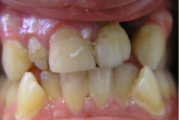

Kaasasündinud hammaste puudumine

Sagedamini puuduvad hambad: teised premolaarid, ülemised lateraalsed intsisiivid, alumised tsentraalsed intsisiivid.